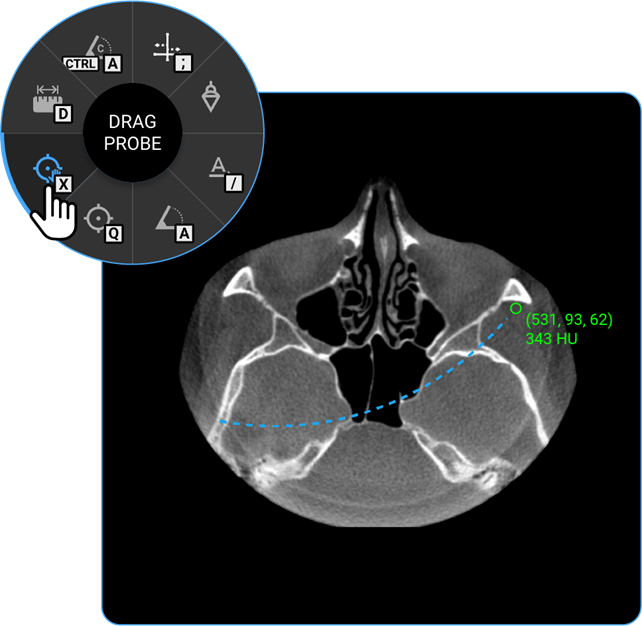

1. Drag Probe: Click on the Drag Probe tool to move a probe point across the image and assess pixel values or other parameters dynamically.

vai